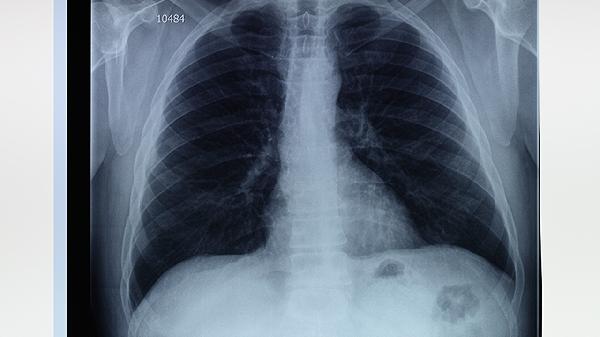

肺部感染性疾病如细菌性肺炎治愈后,局部肺泡壁可能发生纤维化修复。这种纤维灶通常边界清晰,直径较小,患者无咳嗽、胸痛等症状。建议每年进行低剂量CT复查,观察病灶是否稳定。

肺结核治愈后常遗留钙化或纤维灶,多见于肺尖部。病灶可能伴随胸膜增厚,部分患者会有轻微胸闷感。确诊需结合结核菌素试验和痰培养,活动期结核需规范使用异烟肼片、利福平胶囊等抗结核药物。

长期接触粉尘、石棉等职业暴露可导致尘肺病,CT显示双肺弥漫性纤维灶。患者可能出现进行性呼吸困难,需脱离致病环境并使用乙酰半胱氨酸泡腾片、吡非尼酮胶囊等抗纤维化药物延缓进展。

特发性肺纤维化等间质性肺病会出现网格状纤维灶,多位于肺外周。典型症状为干咳和活动后气促,确诊需经支气管镜活检。治疗可选用尼达尼布软胶囊联合氧疗,重症需考虑肺移植。